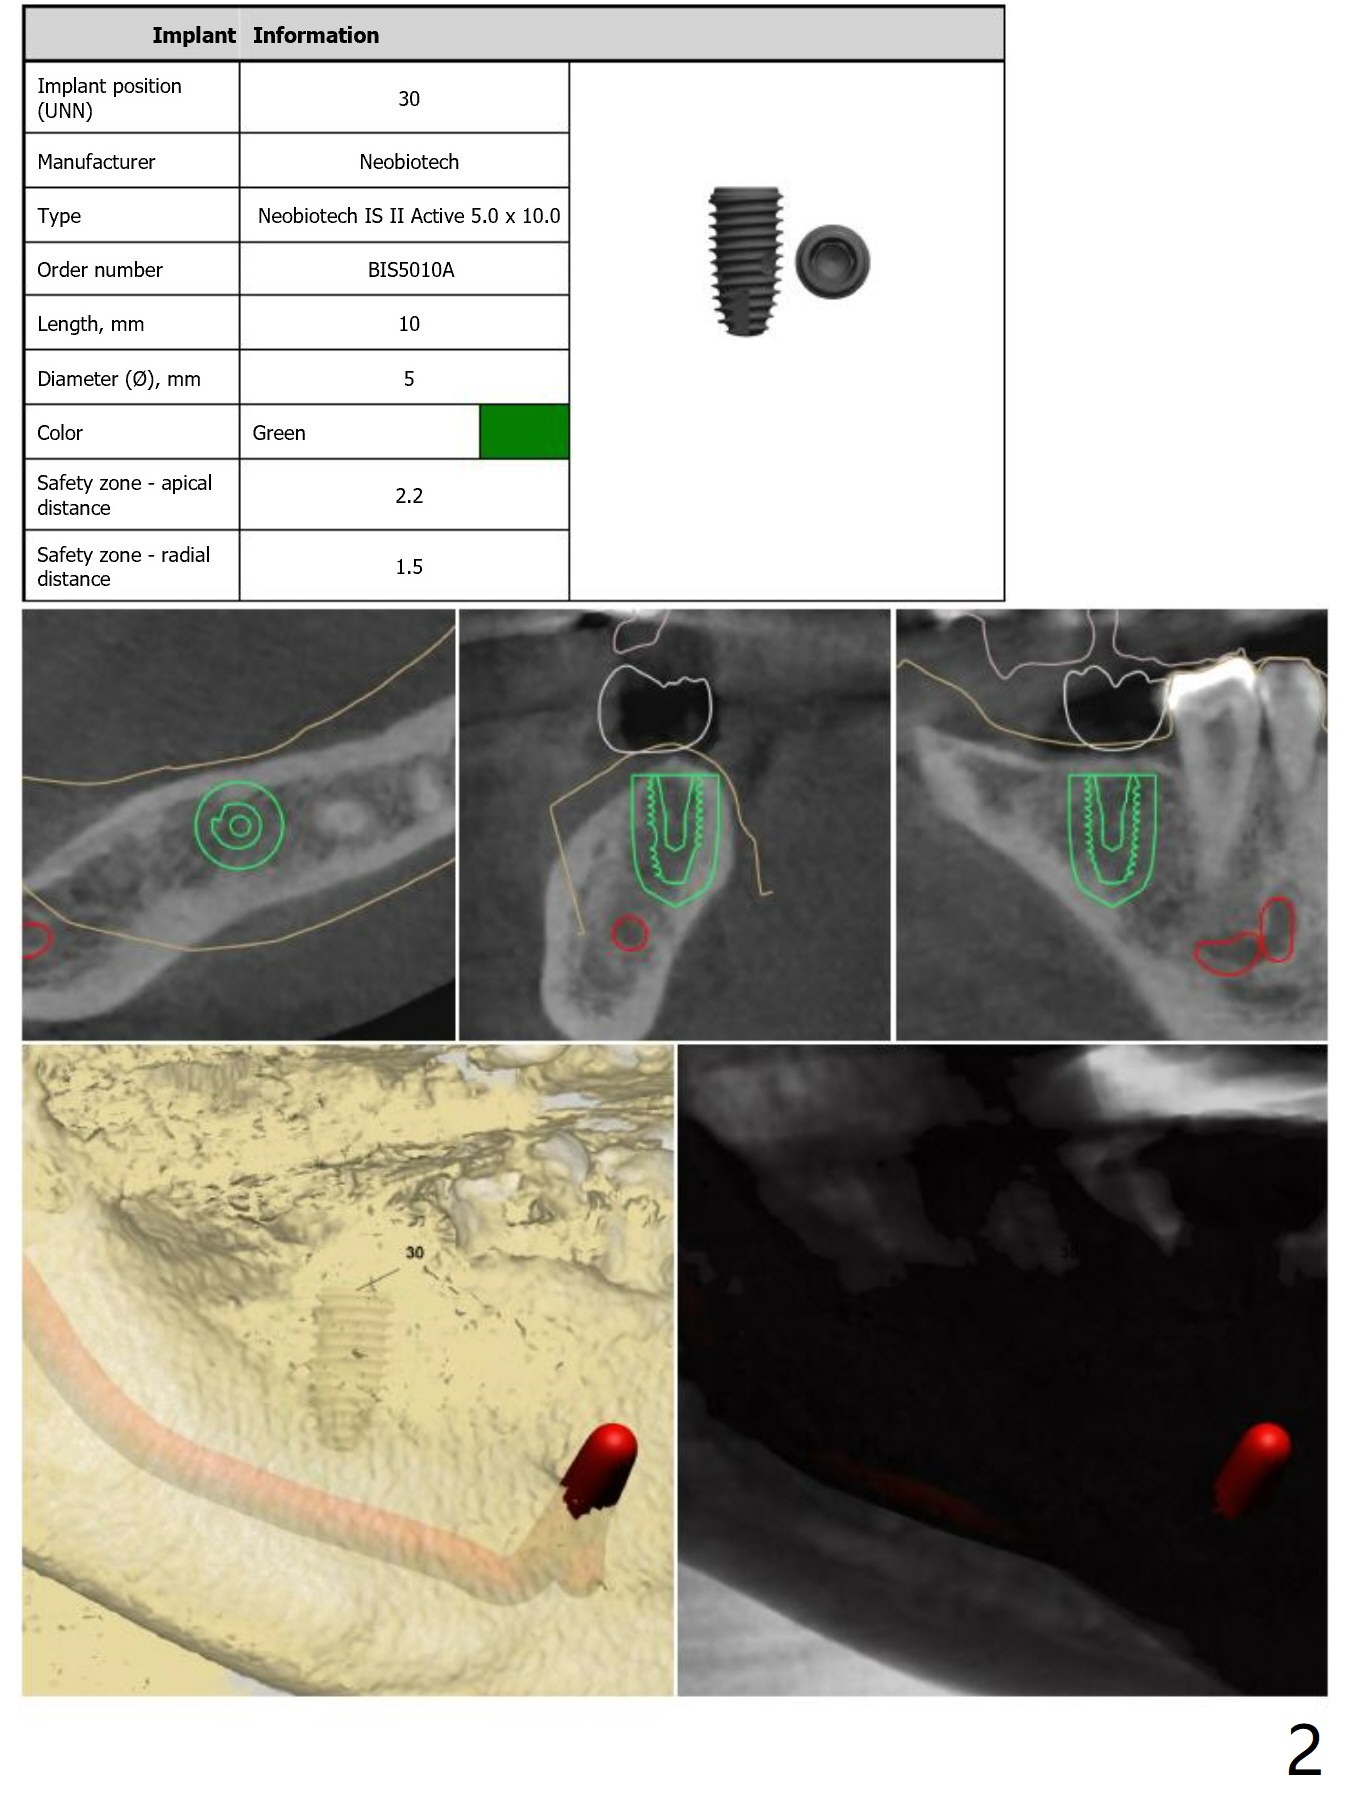

Guide Design for #30

Return to Lower Molar Immediate Implant, Armaments 30 Placement